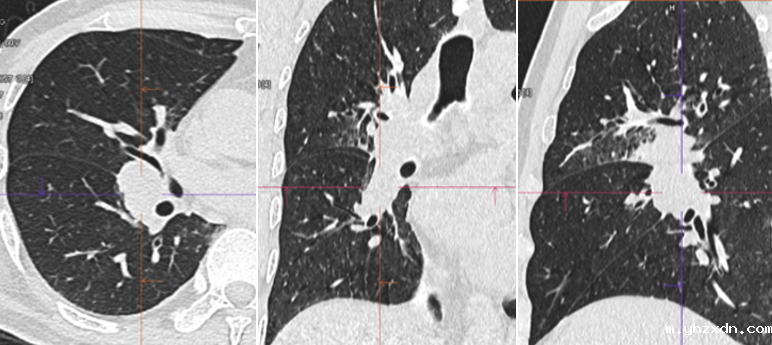

胸部CT结果显示,L先生右肺门区域存在明显肿块,导致右肺中叶出现阻塞性肺炎和阻塞性肺气肿。此外,纵膈部位多发淋巴结肿大,部分淋巴结甚至出现融合(图二)。通过三维重建技术,医生发现肿块已跨越斜裂生长,侵及右肺中叶及下叶(图三)。

(图三)

至此,影像学检查基本确定L先生患有右肺门恶性肿瘤伴纵膈淋巴结转移及脑转移。为了进一步明确肿瘤分期,医院当天为L李先生安排了PET/CT检查。结果显示,右肺门肿块、纵膈淋巴结及脑部肿块的FDG代谢水平异常增高,提示肿瘤恶性程度较高。幸运的是,全身其他部位未见明显转移性病灶,这为后续治疗提供了积极信号。